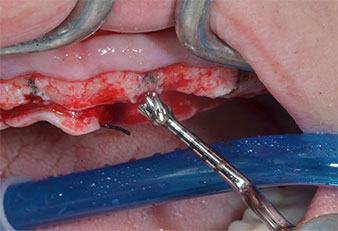

Due to the relatively hard bone (D2) in this area, the 10 mm long implant sites at positions 11 and 21 were finalized with a 4 mm diameter rotary drill, in combination with a W&H WS-75 L surgical contra-angle handpiece, the W&H Implantmed implant motor and the optional W&H Osstell ISQ module. In contrast, due to the soft bone the posterior sites were prepared to a final 3 mm diameter using the Piezomed I3P instrument. The implants were finally placed transgingivally to osseointegrate for three months (Figs. 6-10). The existing denture was retained on four provisional implants (Fig. 8).